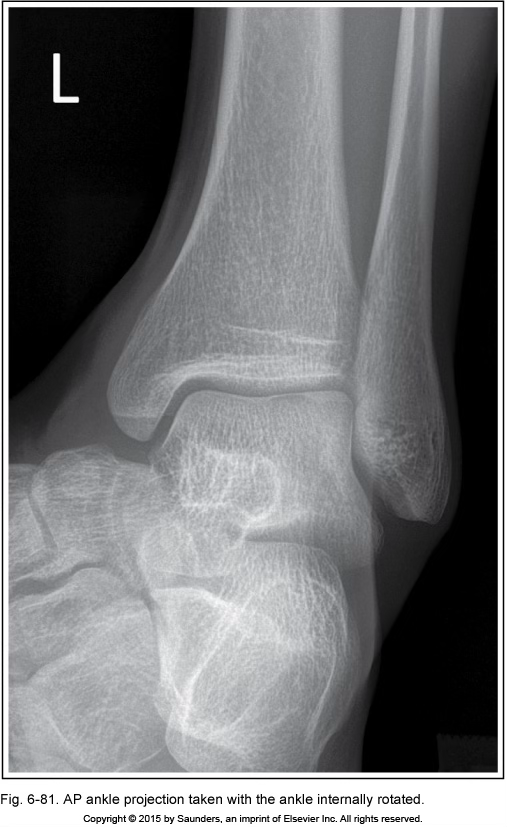

AP ankle

ankle internally rotated

looks like a mortise